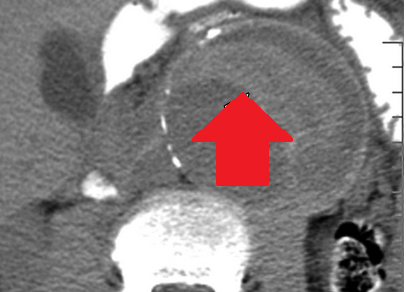

Αυτόματη ρήξη/αιμορραγία νεφρού — νεφροκυτταρικό καρκίνωμα (Ευγενική παραχώρηση Dr. V. Penopoulos)